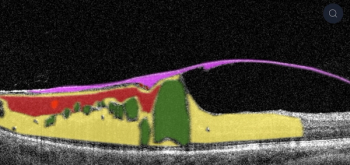

The company's AI cloud-based platform is available via a browser to any eye care professional in the world. The artificial intelligence algorithm was trained on millions of graphically labeled OCT scans collected from ophthalmic clinics.